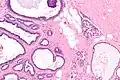

Micrograph of collagenous spherulosis with the characteristic histomorphology - intratubular eosinophilic material with a spoke-like arrangement. H&E stain.

Collagenous spherulosis is characterized by a tubular/cribriform architecture with intratubular eosinophilic material that classically is arranged like the spokes of a wheel ("radial spikes"). There is usually no mitotic activity, and two cells populations (epithelial & myoepithelial) are present, like in benign breast glands.

The lesions are typically small (less than 50 spherules per lesion, less than 100 micrometers in size) and may be multifocal.